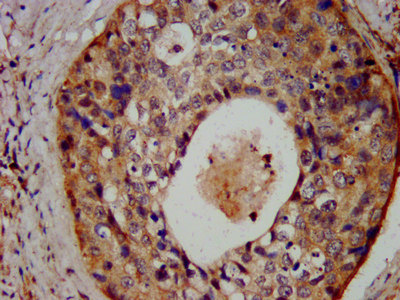

IHC image of CSB-PA614263LA01HU diluted at 1:300 and staining in paraffin-embedded human cervical cancer performed on a Leica BondTM system. After dewaxing and hydration, antigen retrieval was mediated by high pressure in a citrate buffer (pH 6.0). Section was blocked with 10% normal goat serum 30min at RT. Then primary antibody (1% BSA) was incubated at 4°C overnight. The primary is detected by a biotinylated secondary antibody and visualized using an HRP conjugated SP system.